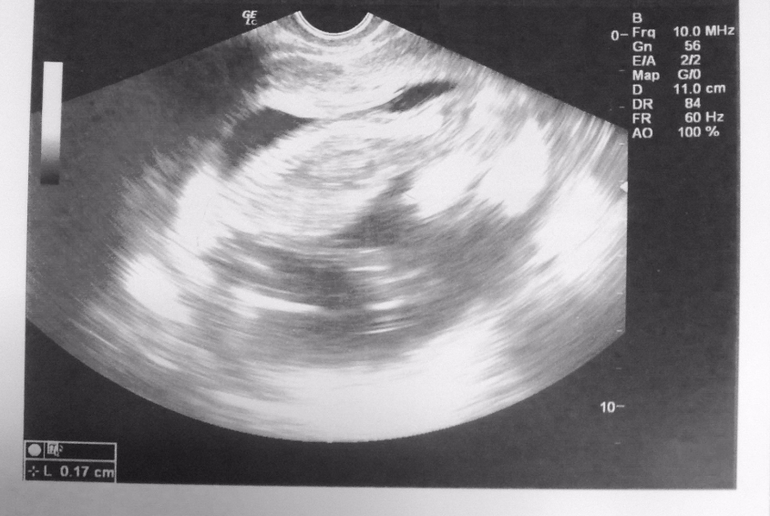

А вот и наш первый скрининг ;)

Пишу отчет с нашего первого в жизни скрининга.

Настроение было отличное, несмотря на не оч хорошее самочувствие вчера, ведь мне предстояла встреча с моим головастиком (теперь я понимаю почему девочки так называют малышей). Голову я увидела оооочень четко на УЗИ!

Затем с результатами узи и фоточками (прикреплю ниже) мы отправились на сдачу крови на ХГЧ и протеин А (РАРР-А) на голодный желудок. Результаты обещали прислать через 2 дня, т.е. послезавтра